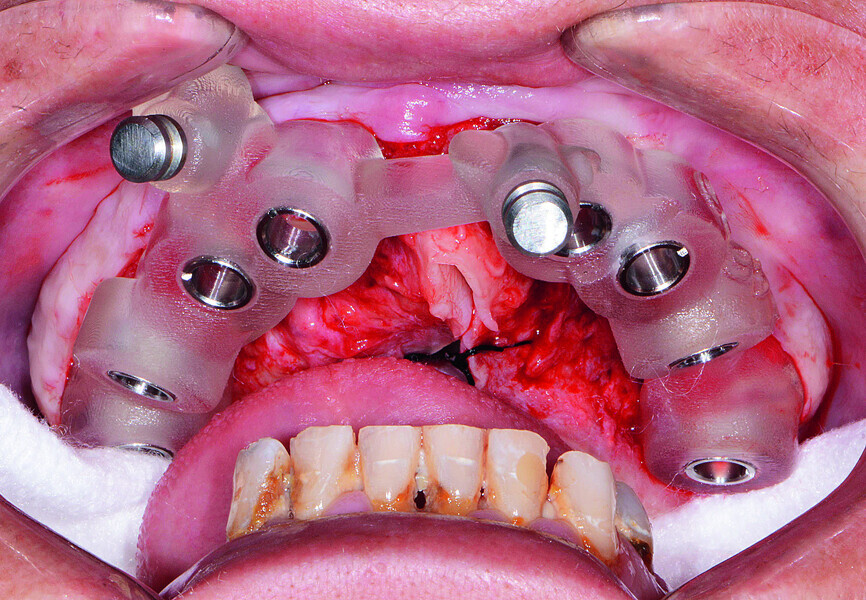

Fig. 14: Mandibular surgical guide stabilised.

Fig. 15: Implants and healing caps with surrounding grafting.